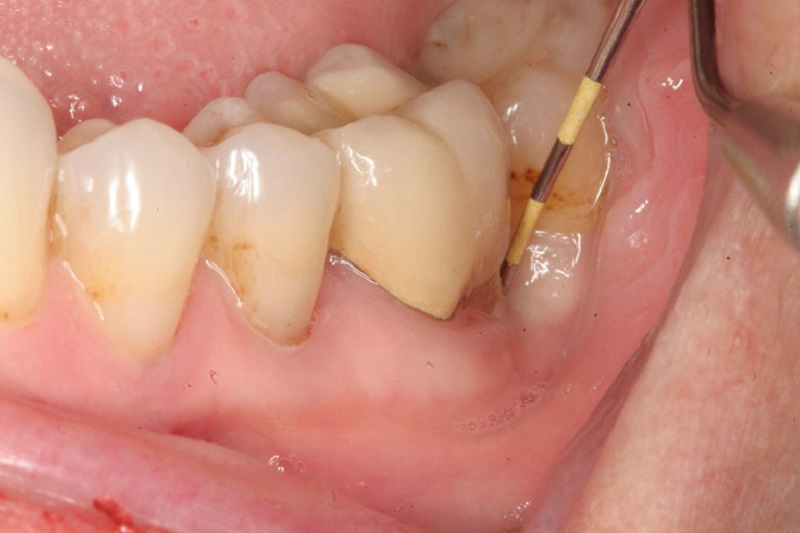

Sau khi kiểm soát cấp tính, bước tiếp theo là điều trị nguyên nhân nền: viêm nha chu và túi nha chu sâu. Bác sĩ sẽ cạo vôi răng, làm sạch dưới nướu và đánh giá mức độ tiêu xương. Nếu túi nha chu sâu, có thể cần điều trị chuyên sâu như làm láng gốc răng hoặc can thiệp nha chu.

Mục tiêu của điều trị nha chu là giảm vi khuẩn, làm nướu bám sát trở lại và loại bỏ “khoang trú ẩn” của vi khuẩn. Khi túi nha chu được kiểm soát, nguy cơ tái hình thành áp xe quanh răng giảm đáng kể.

Ngoài ra, bác sĩ sẽ hướng dẫn kỹ thuật vệ sinh phù hợp như dùng bàn chải kẽ, chỉ nha khoa và nước súc miệng hỗ trợ. Đây là nền tảng để kết quả điều trị bền vững, hạn chế tái phát và bảo tồn răng thật lâu dài.